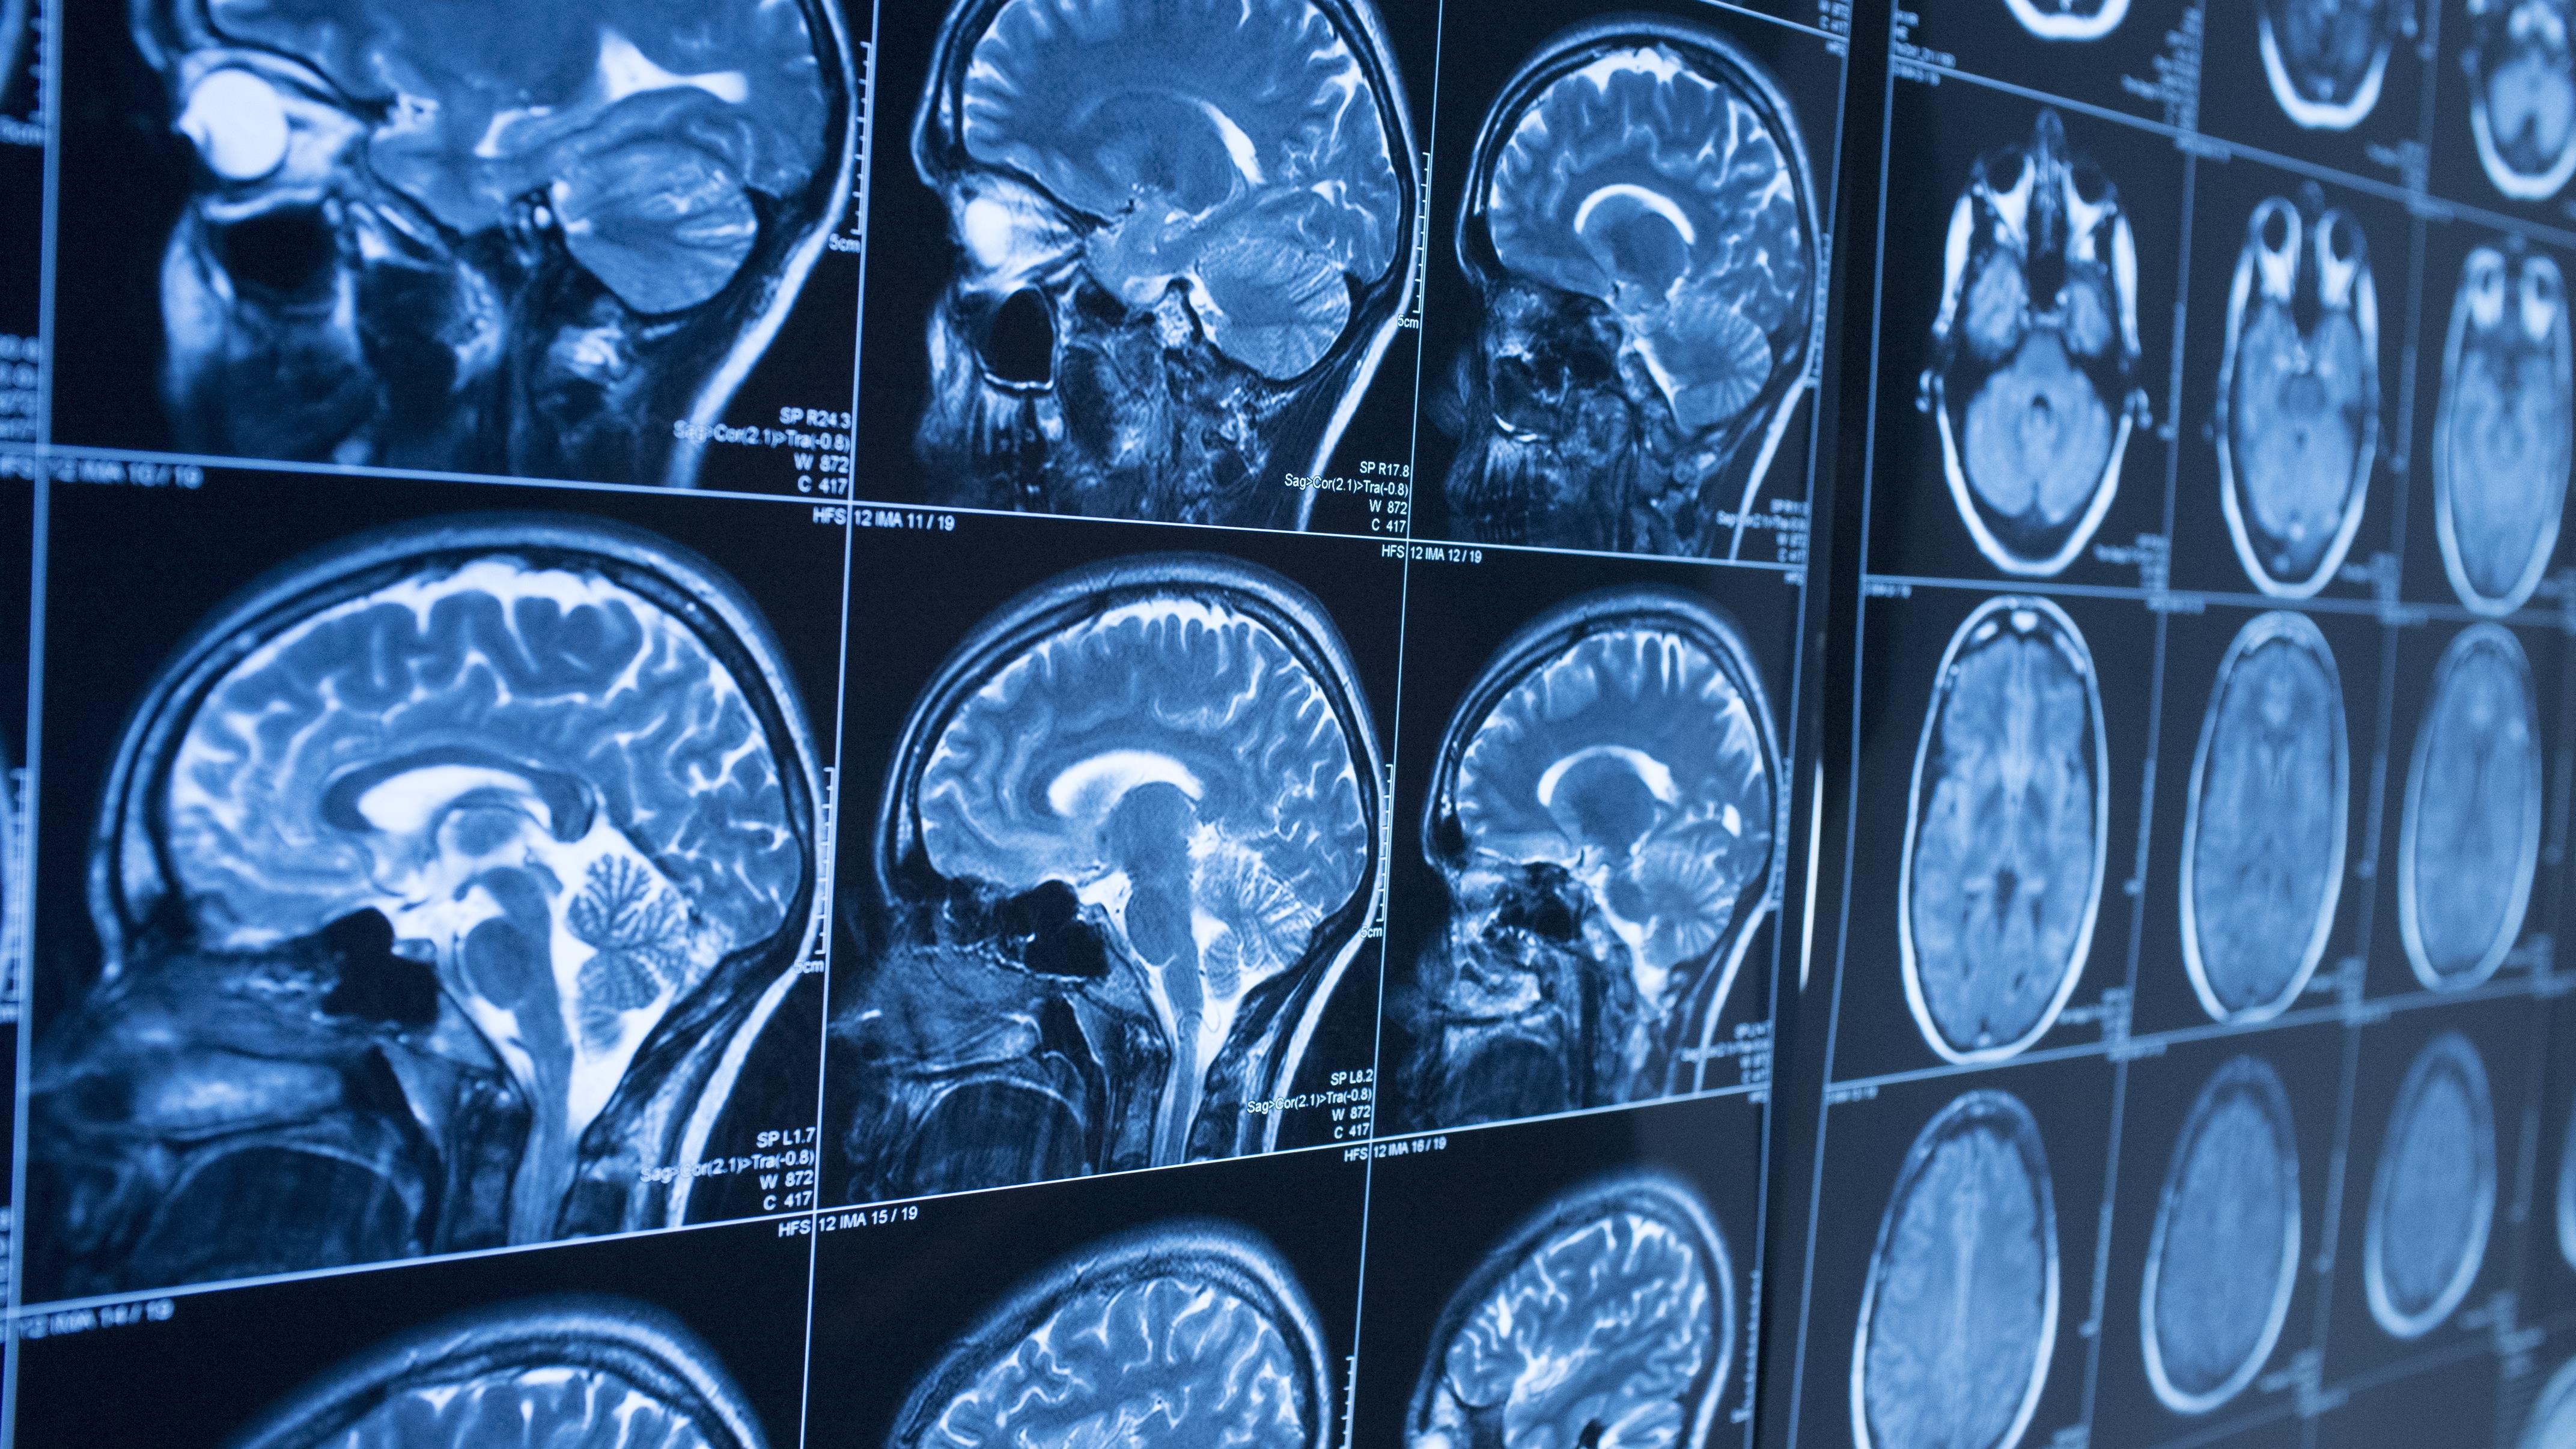

Utiliser l’IA pour écrire réduirait l’activité cérébrale de 55 %.

Autrement dit, plus on délègue… moins on muscle son cerveau.